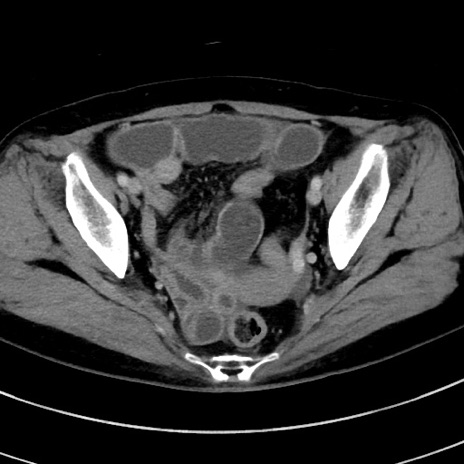

症例9(横断像)

【症例】 60歳代女性

【主訴】むかつき、みぞおちの痛み

【現病歴】3日前よりむかつきがあり、食事がとれない。

【既往歴】糖尿病

【身体所見】発熱なし、心窩部圧痛軽度あるも、腹膜刺激症状なし。

【データ】WBC 7400、CRP 1.92